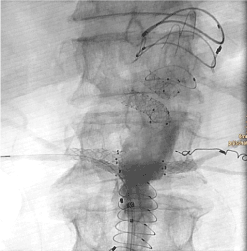

Figure 5. Intraoperative x-ray image at the end of the procedure. Main stent graft, aortouniiliacal prosthesis, sidebranches in situ. Note the coil in the small-caliber left renal artery

After surgical preparation of the left groin, a small-caliber renal artery on the left side was embolized with detachable coils (Interlock, Boston Scientific). After insertion of the individually designed fenestrated main graft tube (Anaconda, Terumo), blood flow to the remaining five visceral vessels – celiac trunk, superior mesenteric artery, left renal artery, superior and inferior doubled right renal artery – was maintained by insertion of covered stent grafts (Viabahn, Gore) through the fenestrations. Finally, an aortouniiliacal prosthesis was implanted (Anaconda, Terumo).

In the final angiogram and in the first postoperative CT-angiogram no early complications or endoleak were found. The peri- and postoperative course was uneventful. The patient was discharged in good general condition on the 7th postoperative day.